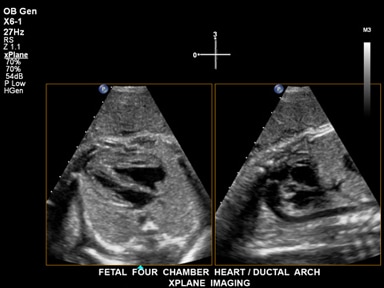

Live xPlaneイメージングは、フル分解能の断面を2断面同時に描出し、通常の2Dイメージングと同じ時間で2倍の臨床情報を取り込むことができます。

これは、Live xPlaneイメージングを使用して提供された、胎児心臓の四腔およびDuctal archを示す2枚の画像です。